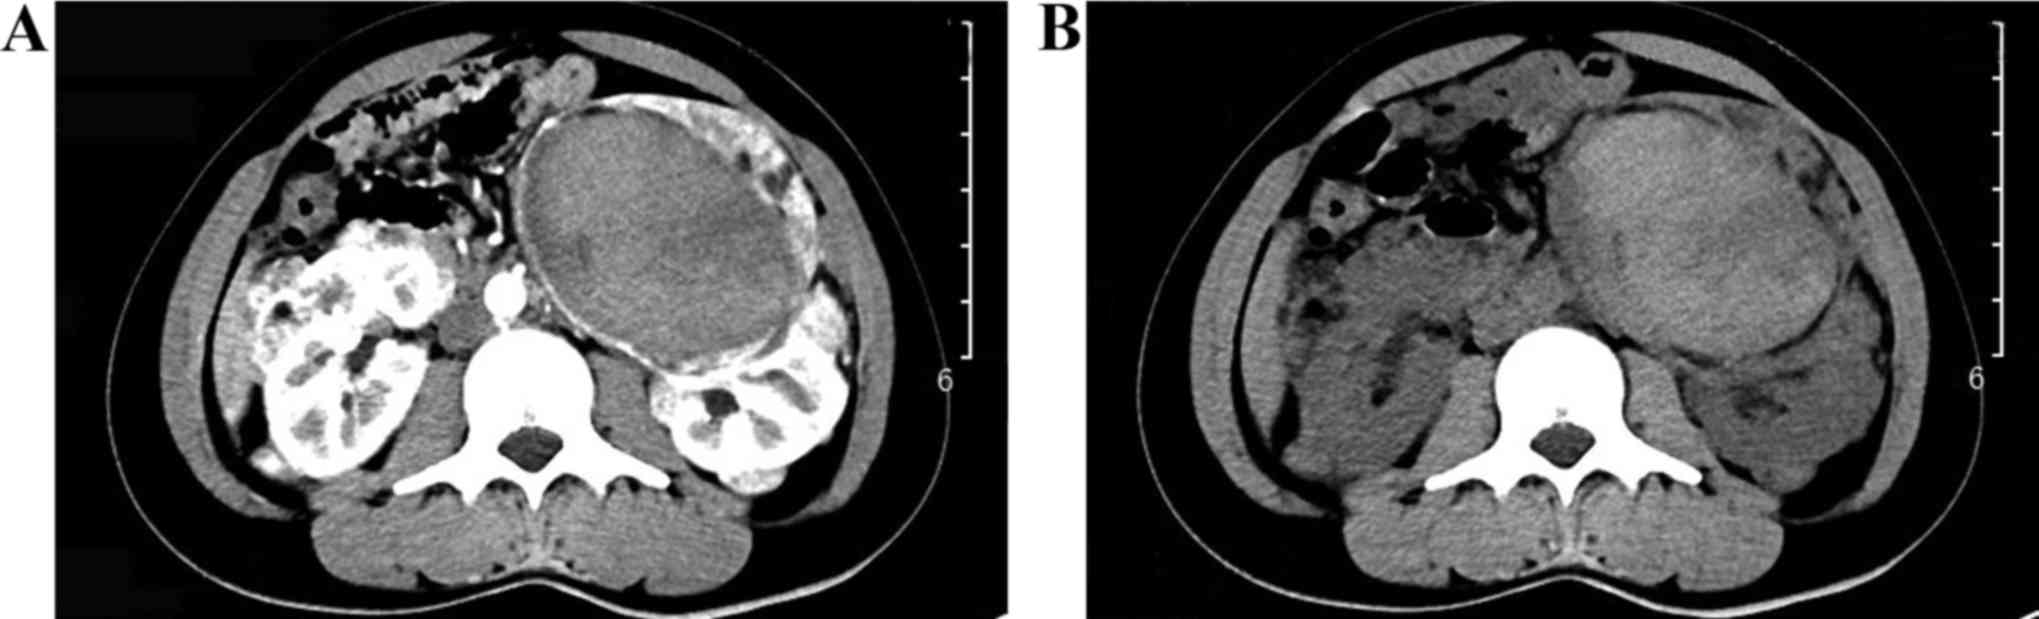

Tuberous sclerosis-associated renal angiomyolipoma: A report of two cases and review of the literature

In the general population, tuberous sclerosis‑associated renal angiomyolipoma (RAML) is a rare benign hamartoma with potentially life‑threatening complications and a poor prognosis. The two patients reported in the present study, who were diagnosed with bilateral RAML and spontaneous rupture of the RAML with tuberous sclerosis, presented with flank pain, abdominal pain, hemorrhage, hematuria and multiple lesions. The two cases are representative examples of the disease, and highlight the importance of determining the risk of acute hemorrhage in the early stages, and the significance of timely and proper treatment.

Figure 1

Figure 2

Figure 3

Figure 4

Figure 5